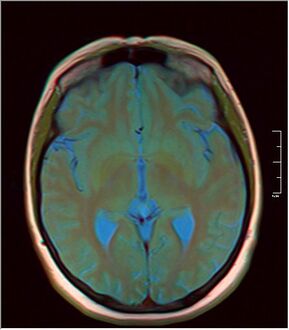

كيسة الغدة الصنوبرية pineal gland cyst هو تكيّس حميد (غير خبيث) في الغدة الصنوبرية، a small endocrine gland in the brain. Historically, these fluid-filled bodies appeared on 1-4% of magnetic resonance imaging (MRI) brain scans, but were more frequently diagnosed at death, seen in 4-11% of autopsies.[1] A 2007 study by Pu et al. found a frequency of 23% in brain scans (with a mean diameter of 4.3 mm).[1]

Despite the pineal gland being in the center of the brain, due to recent advancements in endoscopic medicine, endoscopic brain surgery to drain and/or remove the cyst can be done with the patient spending 5-10 nights in the hospital, and being fully recovered in weeks, rather than a year, as is the case with open-skull brain surgery.[2]